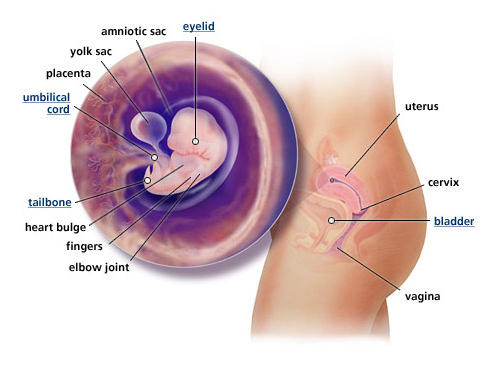

Perkembangan janin 5 minggu - Panduan untuk ibu hamil | theAsianparent Indonesia

Perkembangan janin 5 minggu - Panduan untuk ibu hamil | theAsianparent Indonesia